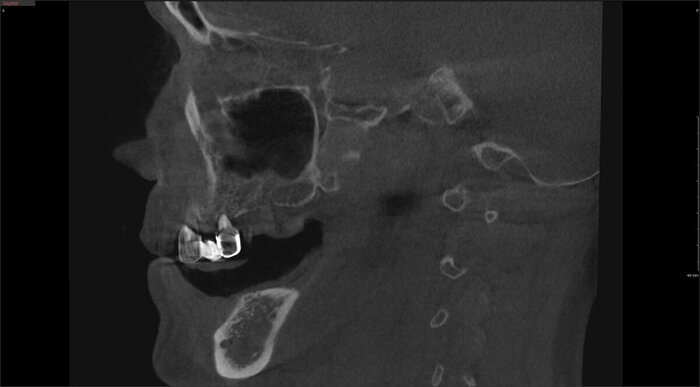

Вот как выглядит цифровая принтованная постановка:

Цифровая принтованная постановка